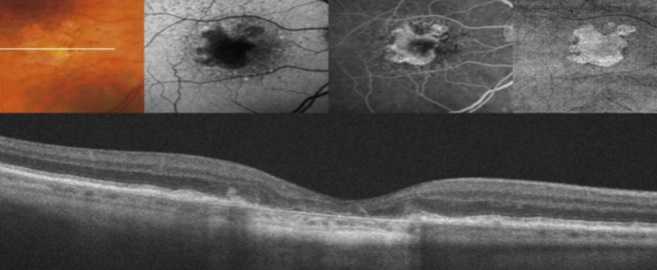

CNV

ingrowth of new vessels extending from the choroid into sub-RPE space in one or more areas

neovascular buds invade & penetrate the degenerated Bruch’s membrane & proliferate beneath the RPE

occult stage/Gass type 1

initial blood flow is very slow through CNVM

fibrovascular PED or late leakage of underdetermined source

breaks through Bruch’s but staying sub-RPE

classic CNV/Gass type 2

CNVM

well defined hyperfluorescence

cartwheel or sea fan appearance

thought to break through RPE & staying sub-retinal

type 1 MNV

fibrovascular PED

late leakage from undetermined source (poorly defined neovascularization)

speckled hyperfluorescence

dye pooling late in study

poorly defined

type 2 MNV

MNV is now b/t neurosensory retina & RPE making the IVFA more obvious & well defined

IVFA shows lacy, well-group area of neovascularization

hyperfluorescent early in study

late leakage

lacy early fill of the MNV during the choroidal & arterial filling phase

may have hypofluorescence corresponding to RPE hyperpigmentation & blood in the outline of the MNV

progressive hyperfluorescence throughout the FA w/o leakage of the margins of the MNV

MNV type 1

MNV type 1

MNV type 1

MNV type 1

MNV type 1

classic CNV

classic & occult CNV

type 2 MNV

MNV type 2

MNV type 2

MNV type 2

MNV type 2

MNV type 2